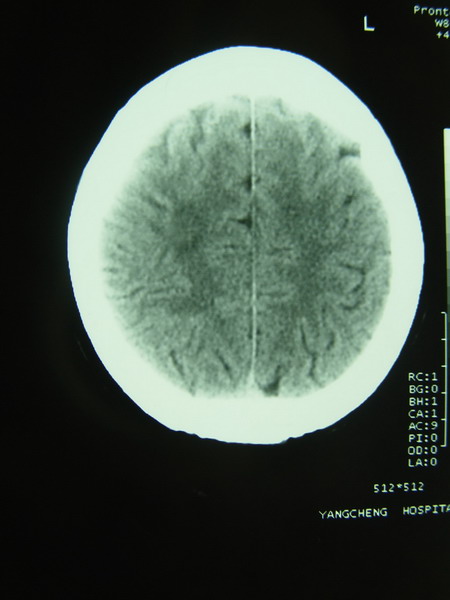

标题: CT12368:女,44岁。突发性左侧肢体麻木4天。 [打印本页]

标题: CT12368:女,44岁。突发性左侧肢体麻木4天。

右侧基底节区腔隙性脑梗塞;右侧顶叶深部及放射冠区病灶考虑机器伪影所致,建议ct增强扫描。

看到黑箭所致的类圆形图形了吧?周围是低密度环形影,用腔隙梗塞来解释很难令人信服。

1确实看到环状低密度影,看症状支持梗塞,最好增强下

枕大池蛛网膜下腔囊肿。右侧半卵圆中心占位性病变,建议强化

应该是机器伪影吧(做一个空气校正或薄层扫描可以改善)。如果是病灶,没有占位效应(排除占位性病变),有4天病史的梗塞灶应该是低密度改变。

支持梗塞,环型低密度灶多层面都有应该是伪影

但从症状支持脑梗塞诊断,但右侧半卵园中心“影”确实用梗塞及占位都不好解释,可以做一下机器校正后薄层扫描。

枕大池蛛网膜下腔囊肿。右侧半卵圆中心占位性病变。